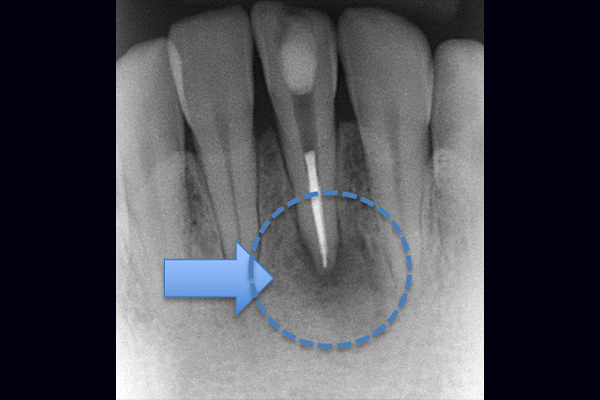

根の横に誤った穴をあけてしまい、気づかずに薬を入れてしまっている。また、器具が破折し、根の先に飛び出ている。

精密根管治療治療終了時歯の側面の穴と根尖はMTAにより緊密に封鎖した。

※本来の根管に薬が入ってることがわかります。